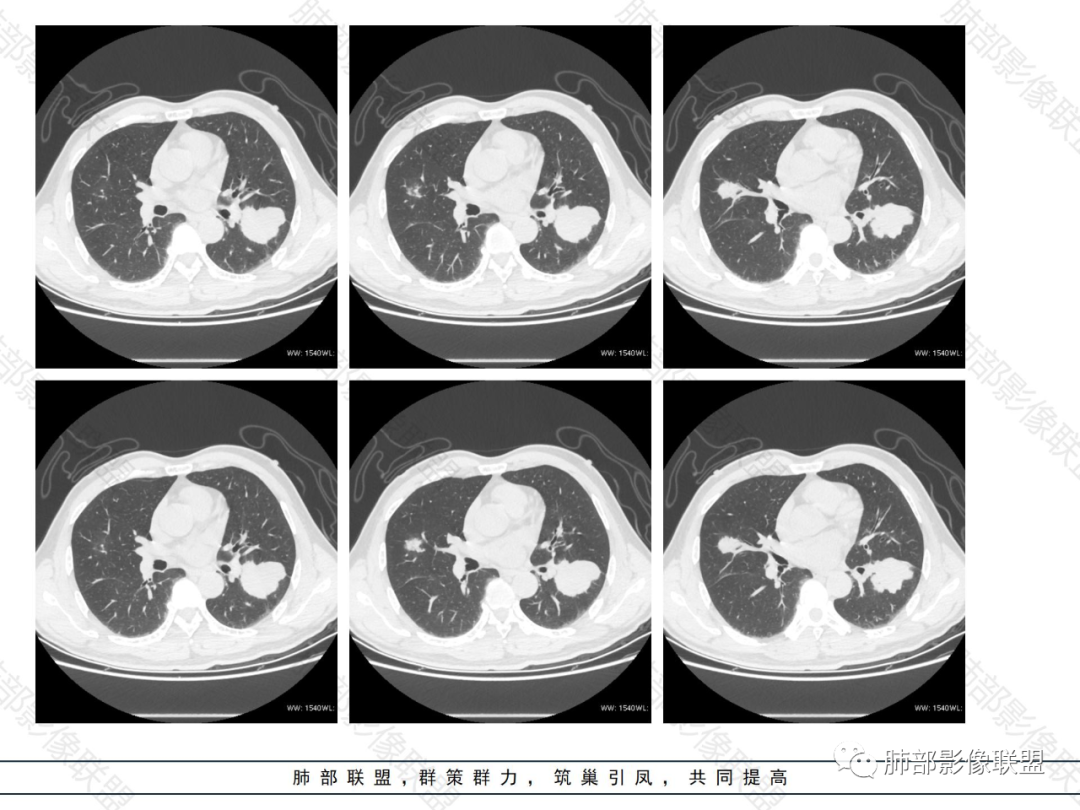

老年男性,半年病史。可惜,没旧片对比。胸膜下多发实变病灶,淋巴细胞,蛋白低。

病灶的影像特点:

外围胸膜下、支气管血管束分布

实变,密度较均匀

病灶的边缘平直、膨隆都有

内部支气管稍扩张,直达远端,或受压变形、移位

均匀强化

内部血管走形自然,稍纤细

支气管通畅、稍扩张、移位——不支持支气管来源

提示间质来源、周围肺实质来源。

疾病谱:淋巴瘤、血管炎性病变、隐球菌

占位效应与收缩性均匀,内部支气管稍扩张,或推移,要考虑淋巴瘤。但因为无前后对比的,如果此起彼伏——警惕血管炎性病变,其次要待排隐球菌。隐球菌不支持的地方支气管扩张过了一点,占位效应过于明显,如下图。

总体还是支持肉芽肿性病变:肿瘤性——淋巴瘤,炎性——血管炎、隐球菌。最后考虑结核病。有前后对比可能有帮助,而且隐球菌多发,这么大的病灶又没有症状,因此待定。